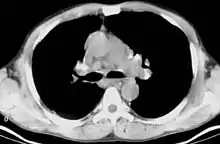

CT scan of the chest showing bilateral lymphadenopathy in the mediastinum due to sarcoidosis.